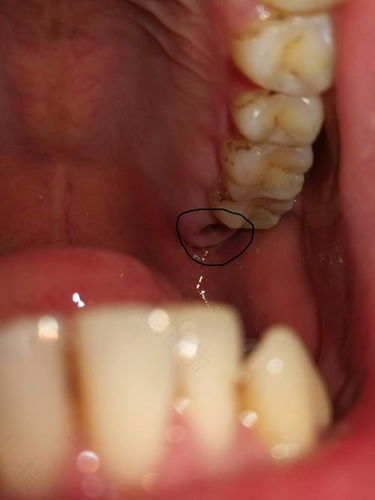

如果牙齿存在缺陷,影响到患者的正常生活,就需要及时的进行拔牙和补牙处理。虽然补牙是一项小手术,但如果不注意饮食和日常注意事项,很可能会导致牙齿方面更大疾病的发生。所以当牙齿存在疾病时,就需要及时的进行补救处理。那么拔完大牙要注意什么?大家一起来看看吧!

拔牙后半个小时内要用棉球进行止血处理。如果出血血流量大,是需要找专业的医生和药物来进行处理的。